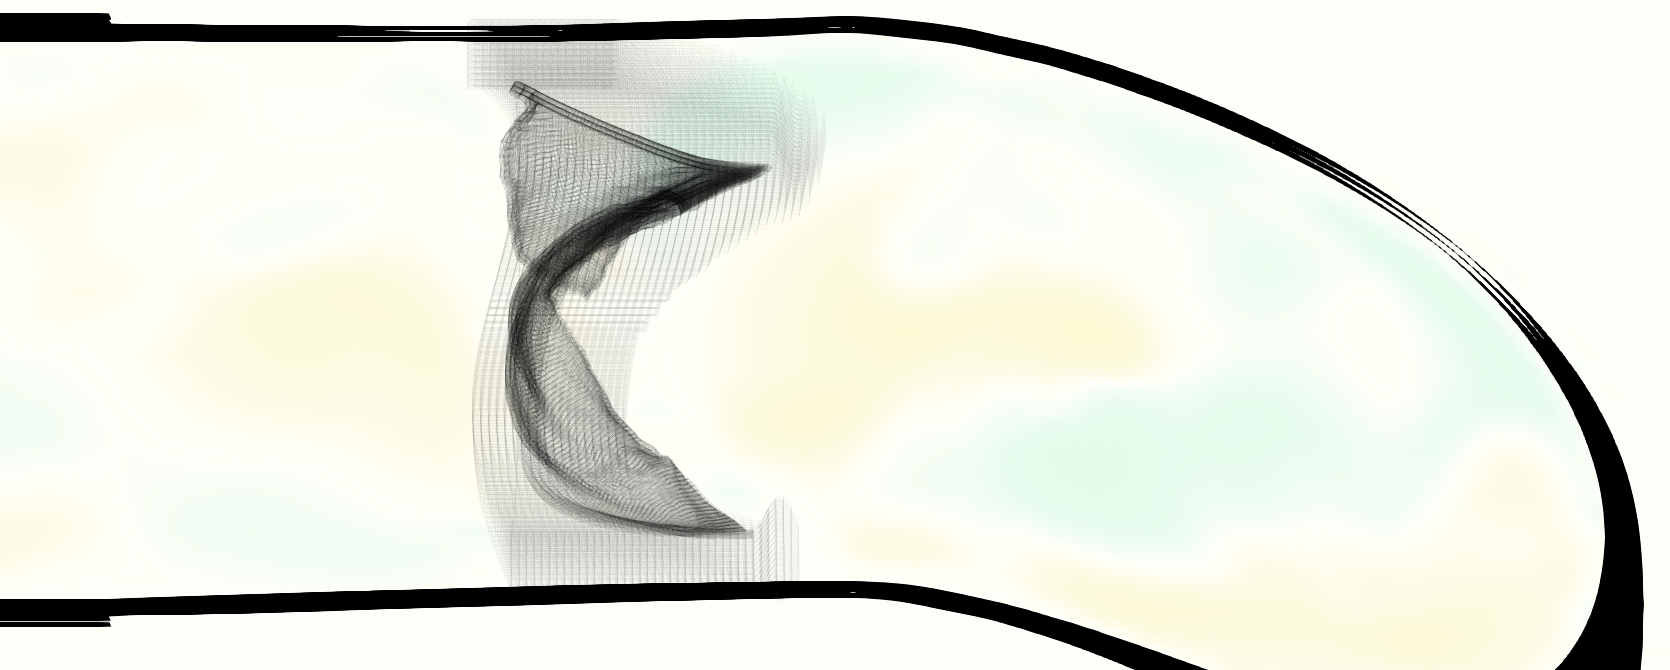

The emergent hemodynamics showed excellent qualitative agreement with experiments. Slice views of the axial component of fluid velocity ( component) in the sagittal plane that cuts through the center of the vessel, parallel to the flow direction, are shown in Figure 5. The flow in both the simulation and the experiment began to accelerate at the same time, with a jet forming through the open valve leaflets. The velocity, angle, and shape of the jet agreed well between the two cases during systole. The simulation captured the slight upward angle of the jet, which was not fully centered in the vessel. It also matched the location where the jet impacts the wall and the slower speed of the jet as it turns with the MPA downstream. As the flow decelerated, the fluid along the interior curve of the vessel reversed first while forward flow persisted where the jet was strongest, as seen in both the simulation and experimental results.

In both the experiment and the simulation, a separation region of reverse flow developed along the interior curve of the vessel under the core jet through the valve. The reverse flow began to develop at the same time in the cardiac cycle and grows throughout systole. The simulation lacked reversed flow in the entire region where reversed flow was present in the experiment, but this region developed some flow separation and had much slower flow than elsewhere in the vessel. Thus, the simulation captured that this is a distinct region from the core jet through the valve opening. There was a smaller amount of slower and slightly reversed flow along the outer curve of the vessel, close to the valve annulus and scaffold support. This region was well-matched between the experiment and the simulation.

Slice views of the (axial) component of fluid velocity in the axial plane, orthogonal to the flow direction, show that the simulation replicated the development of the jet over the cardiac cycle. At each phase, the simulation matched the forward speed of the core of the jet and the locations of reverse flow back towards the valve annulus. While there are some differences in the shape of the jet at certain phases and locations, the simulation clearly produced the general dynamics of the cardiac cycle that are seen in the experiment.

At = 0, the axial slice directly at the valve annulus shown in columns 1 and 2 in Figure 6, there was excellent agreement between the simulation and experiment over the cardiac cycle in the speed and shape of the jet through the valve. In both cases, the axial velocity increased as the flow accelerated during systole and the valve leaflets opened, then decreased during diastole with slight negative velocity before the valve leaflets were fully closed. The forward flow through the valve annulus did not form a full circle, but rather developed a triangular shape with a point of the triangle forming along the interior curve of the vessel, at the bottom of the axial slices. At = 0, the points of this triangular jet shape aligned with the commissures of the valve. This shape persisted during peak systole and was well-matched by the simulation.

The axial slice = 0.625 cm, shown in columns 3 and 4 in Figure 6, cut through the support scaffolding of the valve and the leaflets when they are open. In the experimental data, the shape of the jet changed as it moved downstream. A triangular shape occurred, but the points were then aligned with the middle of each open leaflet as opposed to the commissures. Those points were also more rounded than they were at = 0. The peak velocity of the jet was faster at = 0.625 cm than at = 0, as the flow accelerated through the open valve leaflets. The simulation produced these features at = 0.625 cm. The triangular shape of the jet shifted similarly, and its speed increased compared to the upstream slice. As the flow decelerated into diastole, the jet shape remained roughly triangular but diminished in intensity before disappearing after valve closure.

The jet continued to develop at = 1.25 cm, an axial slice immediately downstream of the valve scaffolding and open leaflets, shown in columns 5 and 6 in Figure 6. In the experimental data, the points of the triangular jet shape extended further towards the vessel wall. In addition, regions of reversed flow developed in the locations downstream of the commissures, resulting in curved sides to the shape of the jet. Each tip of the jet was unique, due to variations in the individual leaflets in the physical bioprosthetic valve. These variations are apparent in the velocity fields, possibly because the jet edges are similar enough cycle to cycle that irregularities are still being captured even with phase averaging. Further discussion of these features can be found in Schiavone et al. [39], which showed that the jet tip shapes occurred in different pulmonary anatomies, demonstrating that they were likely due to inherent properties of each leaflet. The leaflets in the mathematical model of the valve are identical, so these nuances in leaflet variation could not be replicated. The simulation did capture some of the extension of the tips of the jet, as they were closer to vessel wall at slice = 1.25 cm than = 0.625 cm. The curves in the triangular sides of the jet were also present in the simulation, though they were less pronounced than the experimental data. At both = 0.625 cm and = 1.25 cm, the jet shape in the simulation was smoother than the jet in experiment. It is possible that the free edges of the leaflets in the mathematical model are not fully replicating the behavior of the physical leaflets of the bioprosthetic valve, in particular the amplitude or frequency of leaflet flutter, leading to the variations seen in the jet shape at = 1.25 cm downstream of the leaflet edges. The simulation, however, does capture the key features of the triangular shape and speed of the jet. Overall, qualitative comparisons demonstrated that the simulation reproduced key features of the flow during systole and diastole.